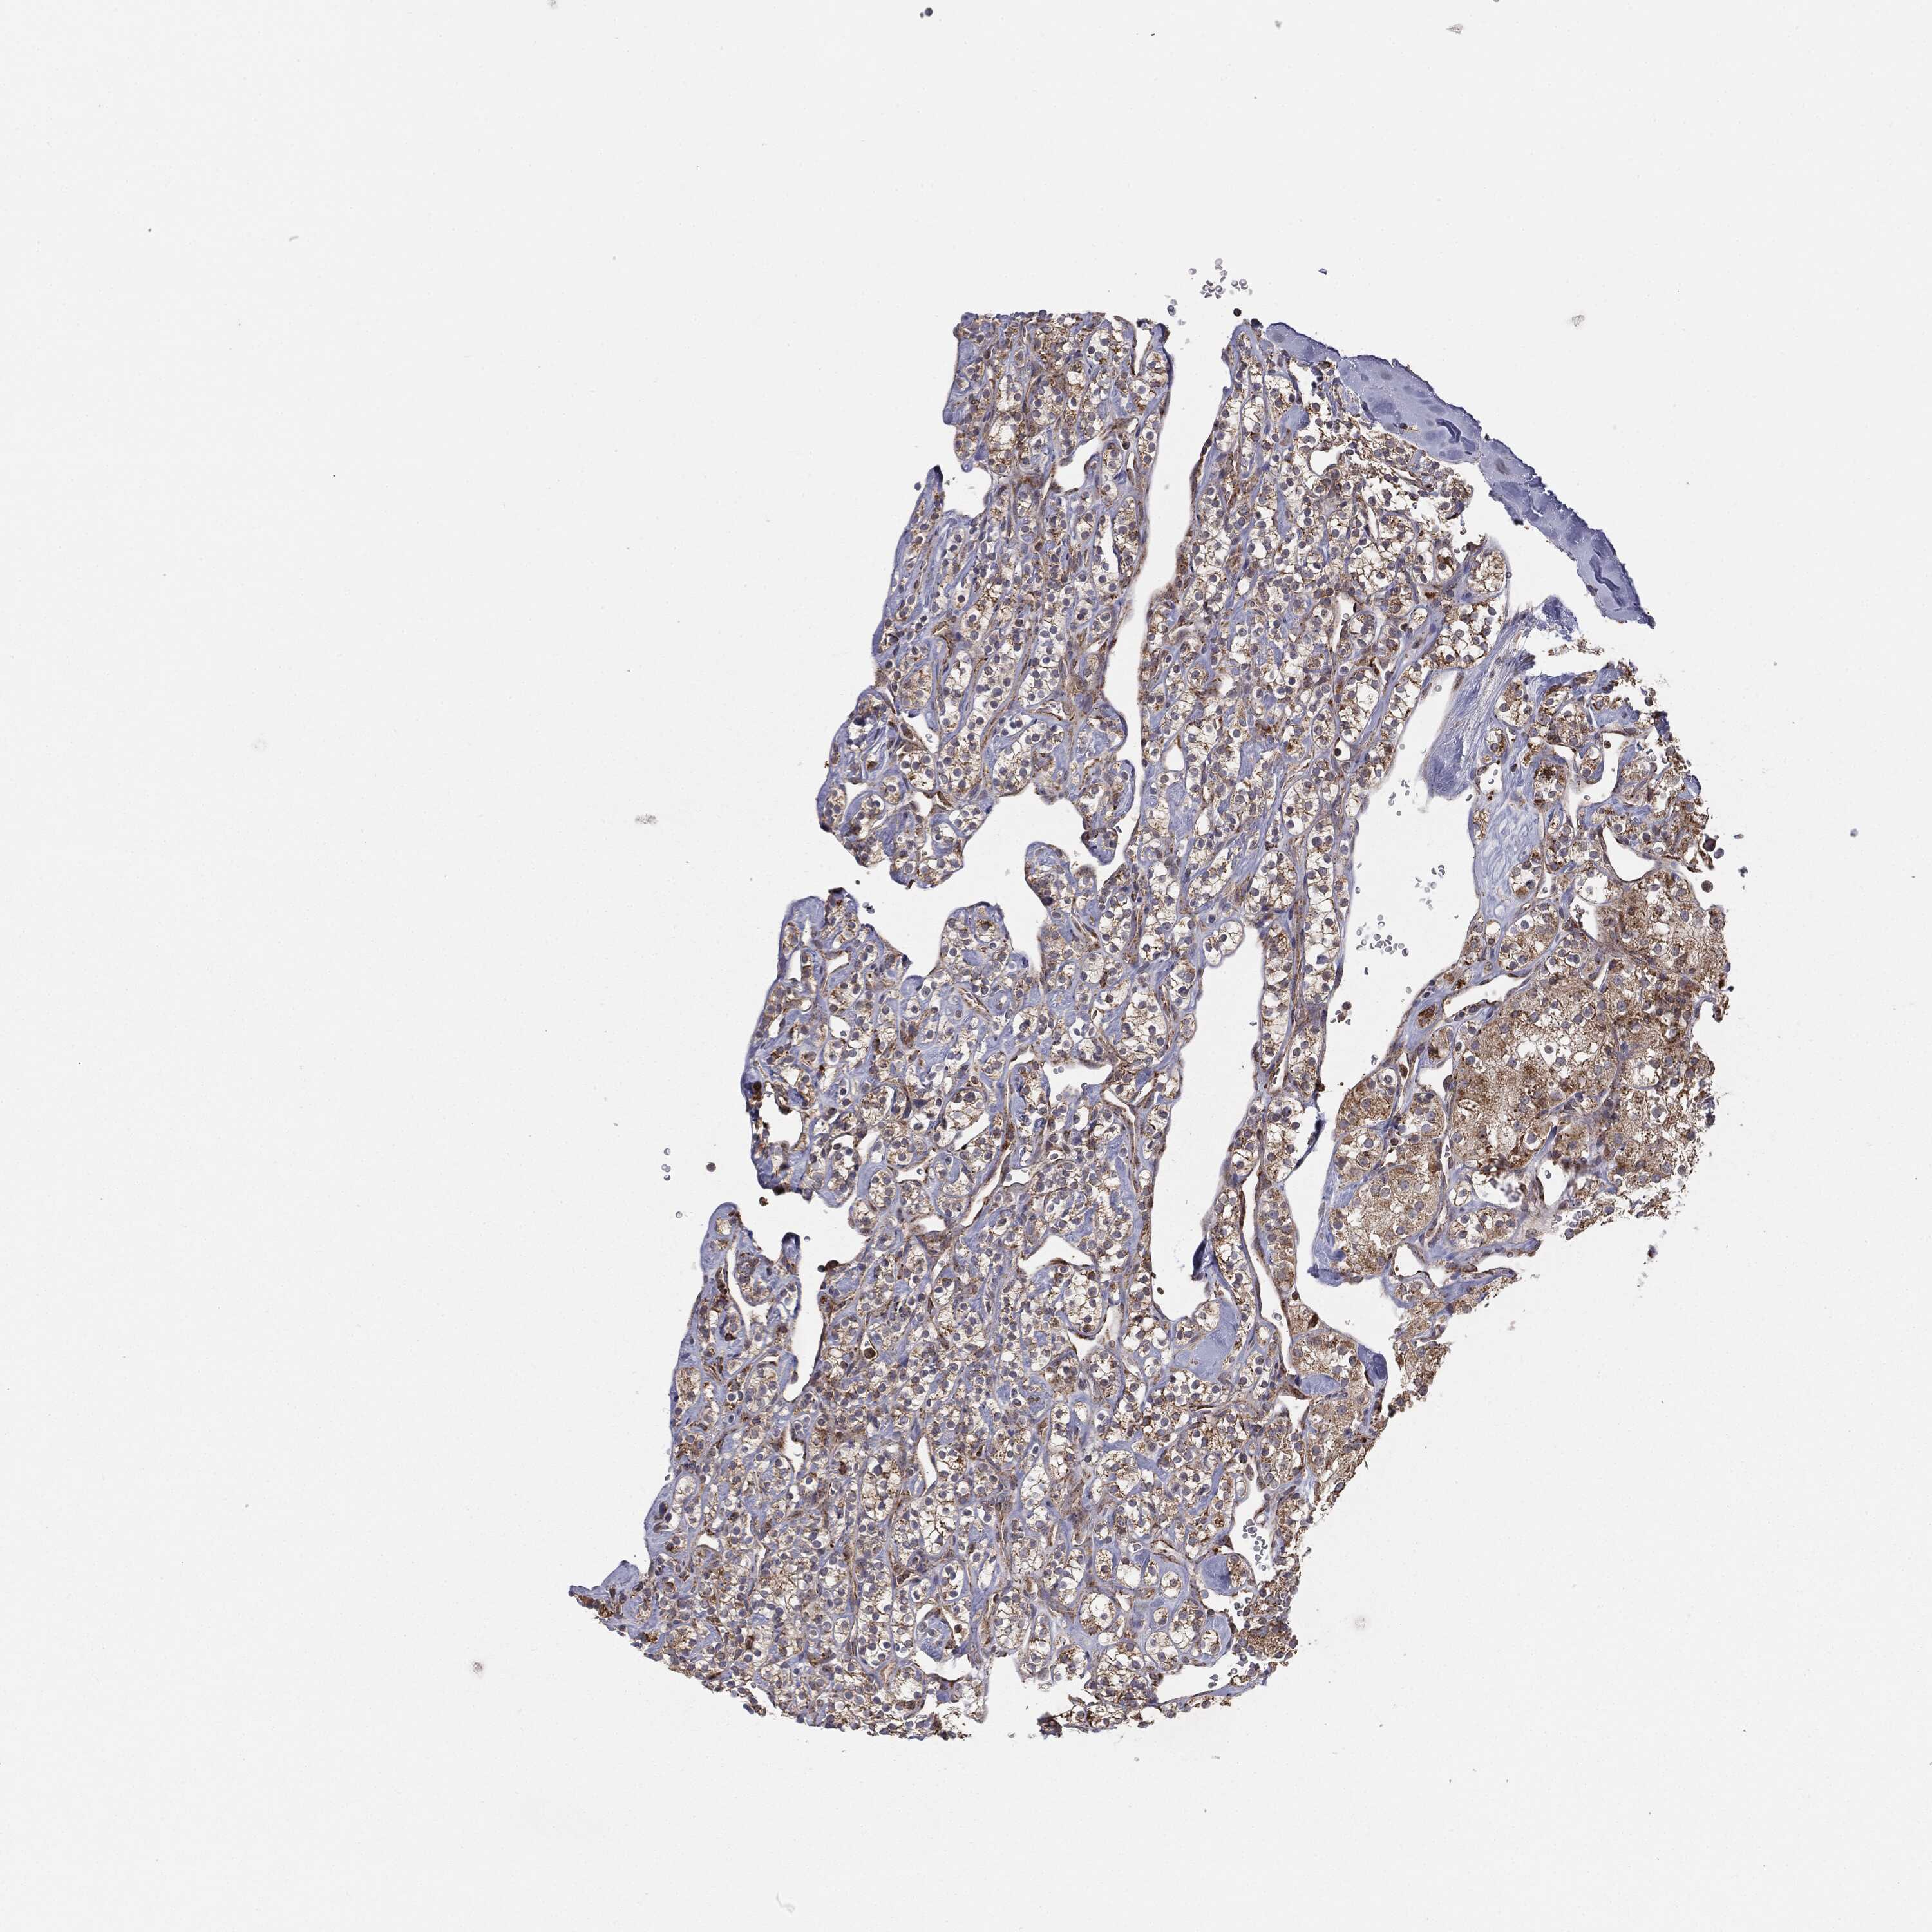

KIDNEY RENAL PAPILLARY CELL CARCINOMA (TCGA) - Interactive survival scatter ploti

The Survival Scatter plot shows the clinical status (i.e. dead or alive) for all individuals in the patient cohort, based on the same data that underlies the corresponding Kaplan-Meier plots. Patients that are alive at last time for follow-up are shown in blue and patients who have died during the study are shown in red.

The x-axis shows the expression levels (FPKM) of the investigated gene in the tumor tissue at the time of diagnosis. The y-axis shows the follow-up time after diagnosis (years). Both axes are complimented with kernel density curves demonstrating the data density over the axes. The top density plot shows the expression levels (FPKM) distribution among dead (red) and alive patients (blue). The right density plot shows the data density of the survived years of dead patients with high and low expression levels respectively, stratified using the cutoff indicated by the vertical dashed line through the Survival Scatter plot. This cutoff is automatically defined based on the FPKM cutoff that minimizes the p-score. The cutoff can be changed by dragging the vertical line or by entering a cutoff value in the square labeled "Current cut-off".

Under the Survival Scatter plot the p-score landscape (black curve; left axis) is shown together with dead median separation (red curve; right axis). Dead median separation is the difference in median mRNA expression between patients who have died with high and low expression, respectively. It is calculated as follows: median FPKM expression of dead patients with high expression - median FPKM expression of dead patients with low expression. This is intended to aid the user in visually exploring custom cutoffs and the associated p-scores and dead median separation.

Individual patient data is displayed and can be filtered by clicking on one or more of the category buttons on the top of the page. Categories describing expression level and patient information include: high, low, alive, dead, female, male and tumor stages. The scale of the x-axis can be toggled between linear and log-scale by clicking on the "x log" button. Mouse-over function shows TCGA ID, patient information and mRNA expression (FPKM) for each patient.

& Survival analysisi

Kaplan-Meier plots summarize results from analysis of correlation between mRNA expression level and patient survival. Patients were divided based on level of expression into one of the two groups "low" (under cut off) or "high" (over cut off). X-axis shows time for survival (years) and y-axis shows the probability of survival, where 1.0 corresponds to 100 percent.

MTOR is not prognostic in Kidney Renal Papillary Cell Carcinoma (TCGA)